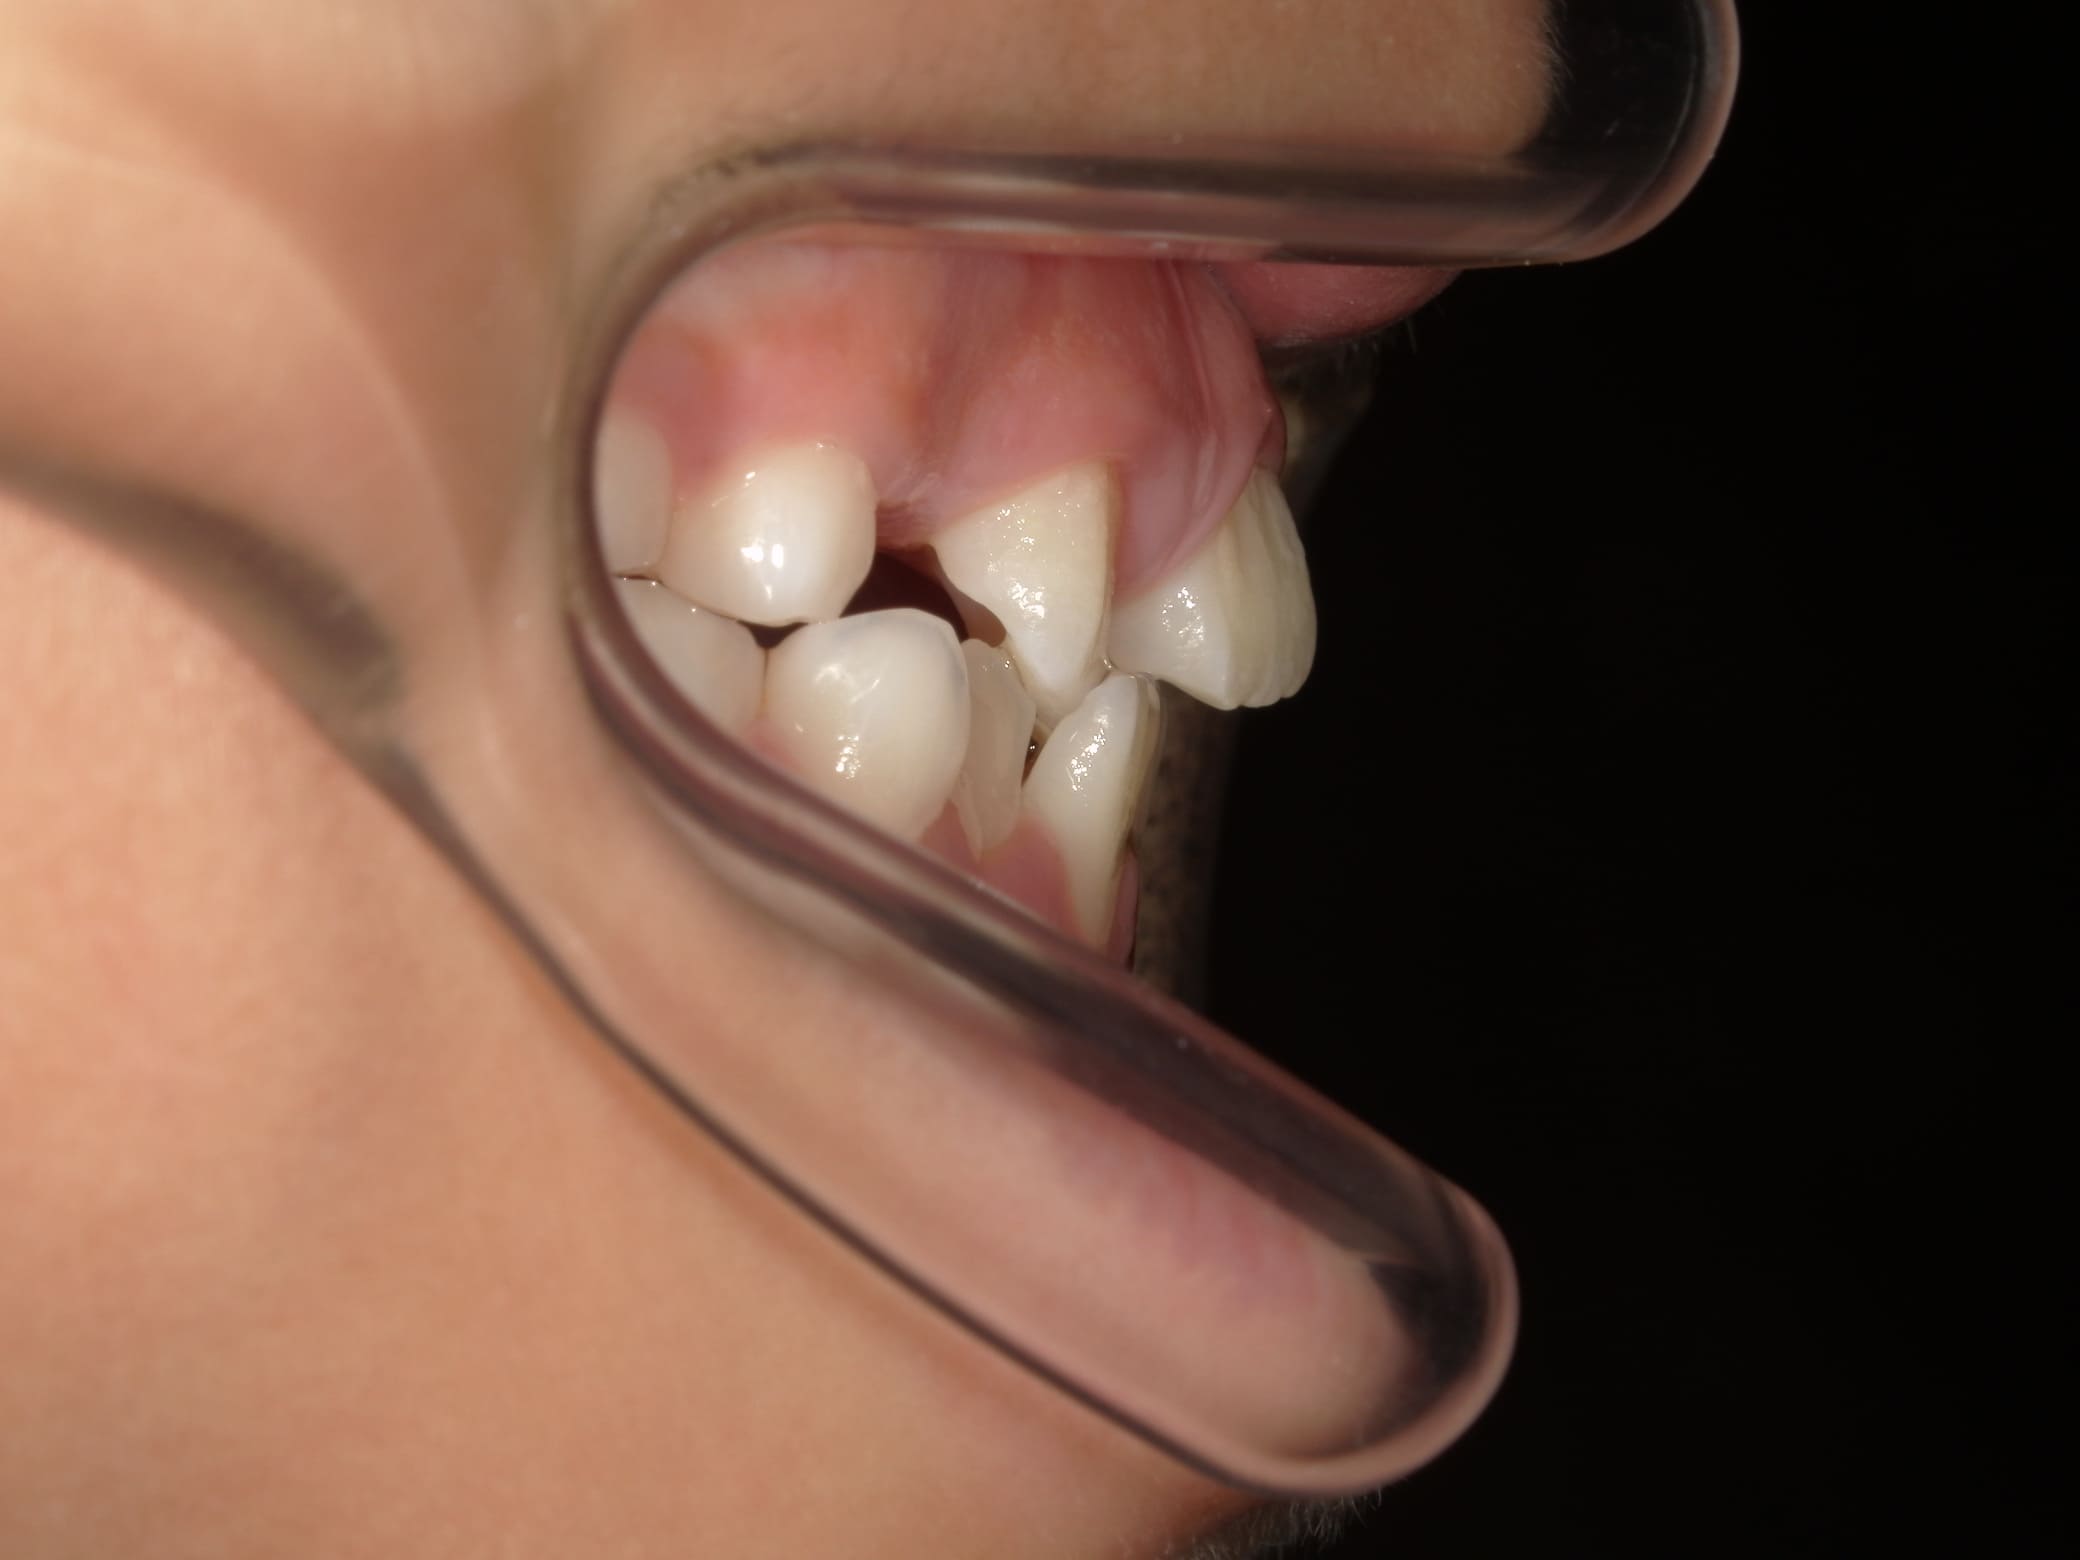

| 年齢・性別 | 7歳1ヶ月の男児 |

|---|---|

| 主訴 | 歯の生えるスペース不足が懸念され、歯列の乱れ(叢生)を整えるために来院された患者様です。 |

| 治療期間・回数 | 1年3ヶ月・11回 |

| 費用 | 420,000円(税別) |